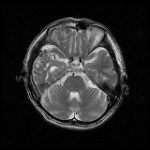

脳血管撮影

手術前

手術後

手術中

モニタリング

手術写真

手術の結果